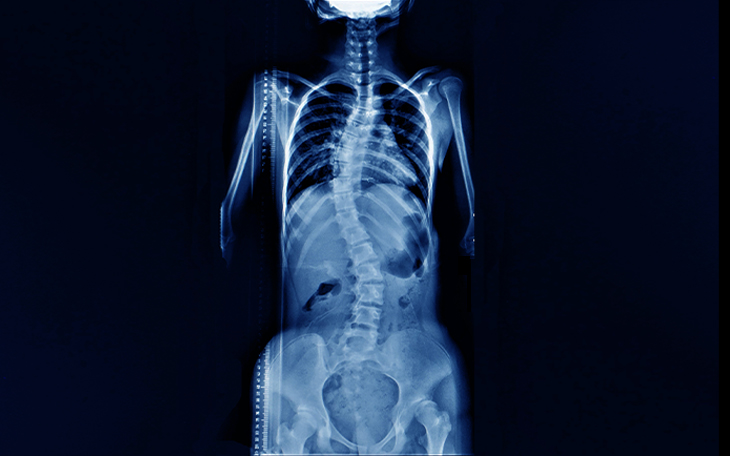

Der Begriff Skoliose bezeichnet eine S-förmige oder C-förmige Verkrümmung der Wirbelsäule in der Frontalebene (sichtbar bei Betrachtung von vorne). Kyphose beschreibt eine verstärkte Vorwärtskrümmung der Wirbelsäule in der Sagittalebene (sichtbar bei Betrachtung von der Seite).

Diese Fehlstellungen können sich im Erwachsenenalter entwickeln oder bereits seit der Kindheit bestehen und sich im Laufe der Zeit verschlechtern. Leichte Krümmungen verursachen oft keine oder nur geringe Beschwerden. Fortschreitende Verkrümmungen hingegen – insbesondere in Verbindung mit anderen Rückenleiden – können starke Schmerzen und Einschränkungen verursachen.

Patienten mit langjähriger Skoliose zeigen oft einen Rippenbuckel und eine Verdrehung des Brustkorbs. Schwerwiegende Verformungen der Wirbelsäule, insbesondere bei starker Seitabweichung oder Verkürzung des Rumpfes, können dazu führen, dass die unteren Rippen mit dem Beckenkamm kollidieren oder mechanisch in Kontakt treten. Zusätzlich können Muskelverspannungen und Druckschmerz auftreten.

Diagnostik

Die wichtigste Untersuchung ist das Röntgenbild in stehender Position, sowohl frontal (AP) als auch seitlich (lateral).

Bildquelle: www.docset.de